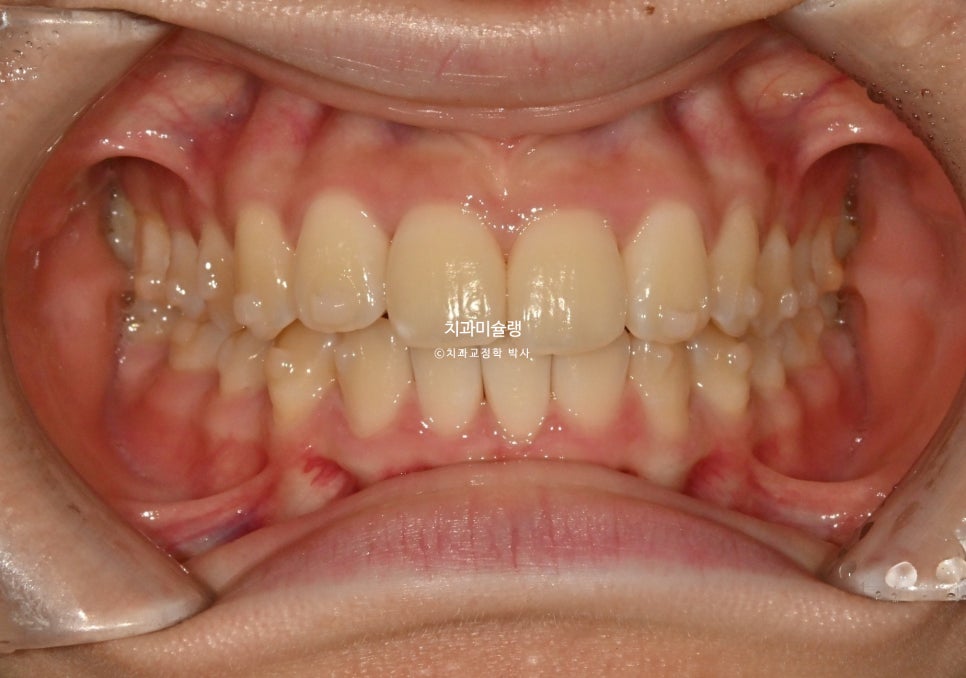

2025년 10월 – 첫 번째 단계 완료

2025년 10월까지 21개 장치를 모두 낀 후 모습입니다.

아래 앞니가 3개인 경우, 위 앞니 중심선이 아래앞니 가운데 치아의 정중앙에 오게 됩니다.

앞니 배열은 개선되었으나 높낮이의 개선이 더 필요하며

배열도 개선이 필요하여 재제작에 들어갔습니다.